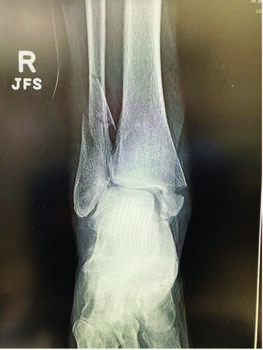

Minimally Invasive Considerations For Fibula Fractures

Traditional fixation methods of the distal fibula consist of an interfragmentary screw with 1/3-tubular plate versus a locking plate of the distal fibula, which require larger incisions. This may place undue stress and trauma along the soft tissues, especially if high-velocity trauma is at fault. There will be cases that require open approaches, but not all do, and the advancement of technology allows surgeons to fixate and reduce these fractures with simple techniques and achieve high patient satisfaction. Descriptions of a typical approach to percutaneous fixation of the fibula utilize a stab incision along the distal-most portion of the lateral malleolus. A guidewire or K-wire placed at the distal-most tip of the lateral malleolus then drives into the medullary canal of the fibula under fluoroscopic guidance. Before the wire crosses the fracture fragment it can facilitate reduction of the fracture fragment. Once confirming proper reduction of the fracture and placement of the guidewire, we use either a medullary fibular nail or 4.5 mm intramedullary screw for fracture fixation. The advantage of the fibular nail is that syndesmotic fixation is still possible, whereas with the screw option, we find there is not enough room to place syndesmotic fixation. The patient selection process is again very important, as with other minimally invasive techniques.

The fibular nail is a newer viable option that technology borrowed from other long bones and transformed the same thought process into the fibula with distal interlocking screws and optional syndesmotic fixation pins, as well as proximal endosteal fixation. The authors prefer a fibular locking nail because of the small incisional footprint and earlier return to activity post-injury. Recent literature also points towards fewer wound complications and need for hardware removal.10,11